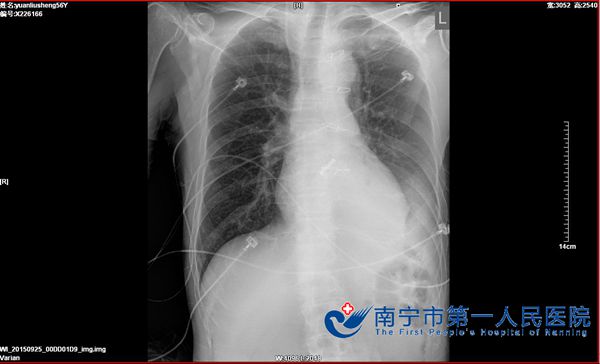

“终于得好好呼吸一口气了”这是今年9月25日袁伯伯拔除气管插管后说的第一句来,其实作为全科医务工作者都知道,对于他来说呼吸好一口气实在太不容易了。原来袁伯3月前行主动脉瓣置换术后因出现肺部感染等较多并发症需长期呼吸机辅助呼吸,曾行气管切开术,待他心脏病情稳定后,却反复出现气喘表现而多次加重心脏功能,需多次入住重症监护室,直至最后一次插管发现困难及经纤支镜检查,才真正证实气管狭窄所致,此翻经历对于袁伯伯来说苦于难言。

气管狭窄,病情较严重,随时可能痰堵气喘窒息可能,科里高度重视于及时组织全院学科讨论。麻醉科、耳鼻喉科、消化内科、泌尿外科、肝胆腺体外科、胸外科各科专家就这病例展开激烈的讨论,考虑气管切开术后瘢痕及肉芽组织生成导致狭窄,有手术治疗指征;最后确定了两个手术方案,一为气管支架植入术,但术后可能出现支架脱落,或再次狭窄的可能,同时对术后生活质量影响较大,目前暂不考虑此手术方案;二为内镜辅助下行气管狭窄疏通术,术中将瘢痕及肉芽组织切除,解除狭窄;但患者狭窄位于声门下,胸廓入口处,位置较低,需保证内镜及器械能到达狭窄位置,同时需保证有足够等操作空间及维持肺部通气,手术难度较大,术中可能出现狭窄疏通不满意,或可能出现窒息,缺氧导致心跳呼吸骤停的风险;同时术后也可能出现再次狭窄的可能。最后一致达成共识决定行内镜辅助下行气管狭窄疏通术。

9月21日经过完善术前准备后,消化内科、肝胆外科及耳鼻喉科通力合作对患者施行手术,仅仅78分钟后手术顺利完成。术后为加固气管狭窄疏通后成果,予连续气管插管呼吸辅助呼吸5天,以便度过气管狭窄部位的水肿应激期。